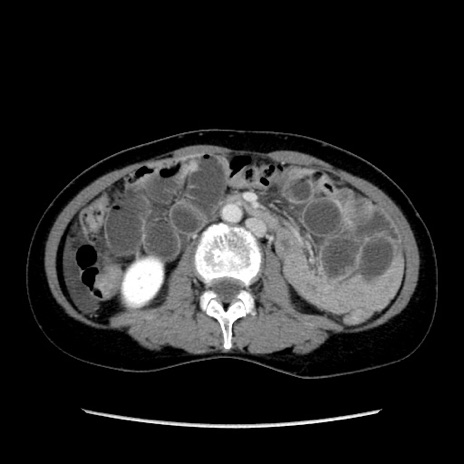

症例32(横断像)

【症例】40歳代 女性

【主訴】上腹部痛、嘔気・嘔吐

【現病歴】約9時間前頃から急に上腹部痛、嘔気、嘔吐が出現。改善しないため救急要請。

【既往歴】子宮頚癌(広汎子宮全摘術、放射線療法)、腸閉塞

【身体所見】腹部:平坦、軟、腸雑音亢進、上腹部を中心に腹部全体に圧痛あり。

【データ】WBC 8400、CRP 0.03